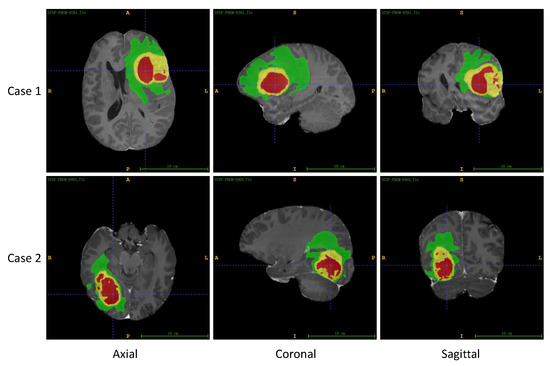

5.1. Segmentation Performance Comparison

5.1.1. Segmentation Metrics Comparison